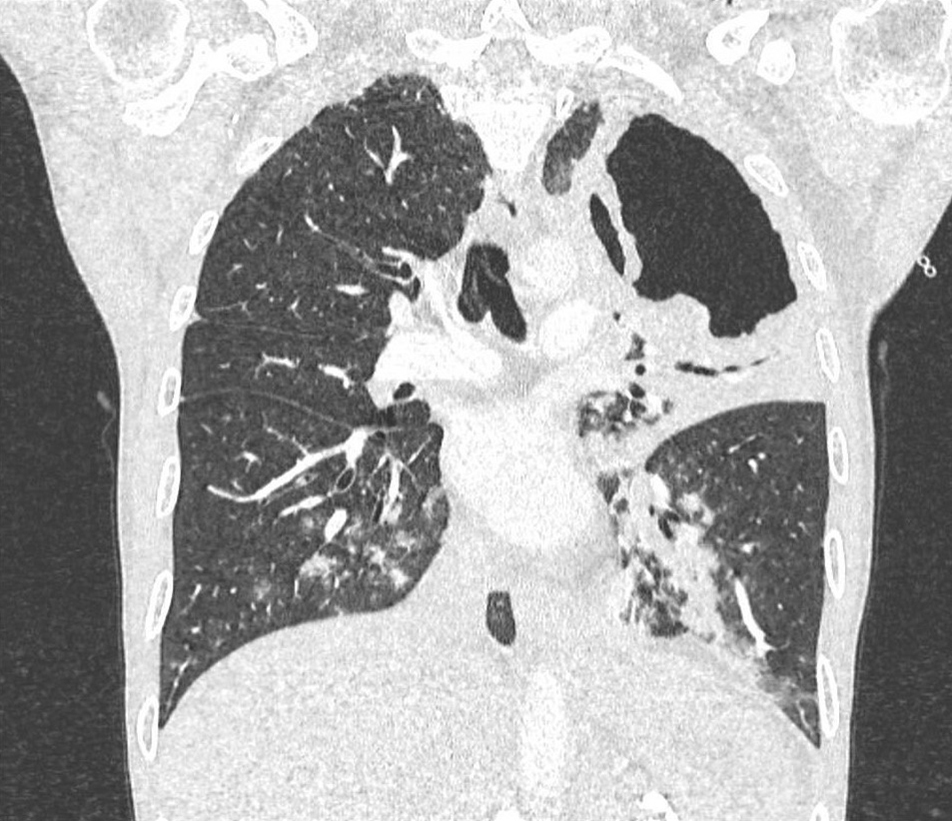

Il s’agit d’un scanner du thorax en coupe frontale et en fenêtre parenchymateuse. On ne retrouve pas d’embolie pulmonaire mais on observe une lésion excavée lobaire supérieure gauche de grande taille avec une condensation alvéolaire péri-lésionnelle avec bronchogramme aérique. Dans les lobes inférieurs, il y a des micronodules centrés sur des bronches (distribution bronchogène ou en arbre en bourgeons).

Figure 2 (Ariane Amoura, La Revue du Praticien)